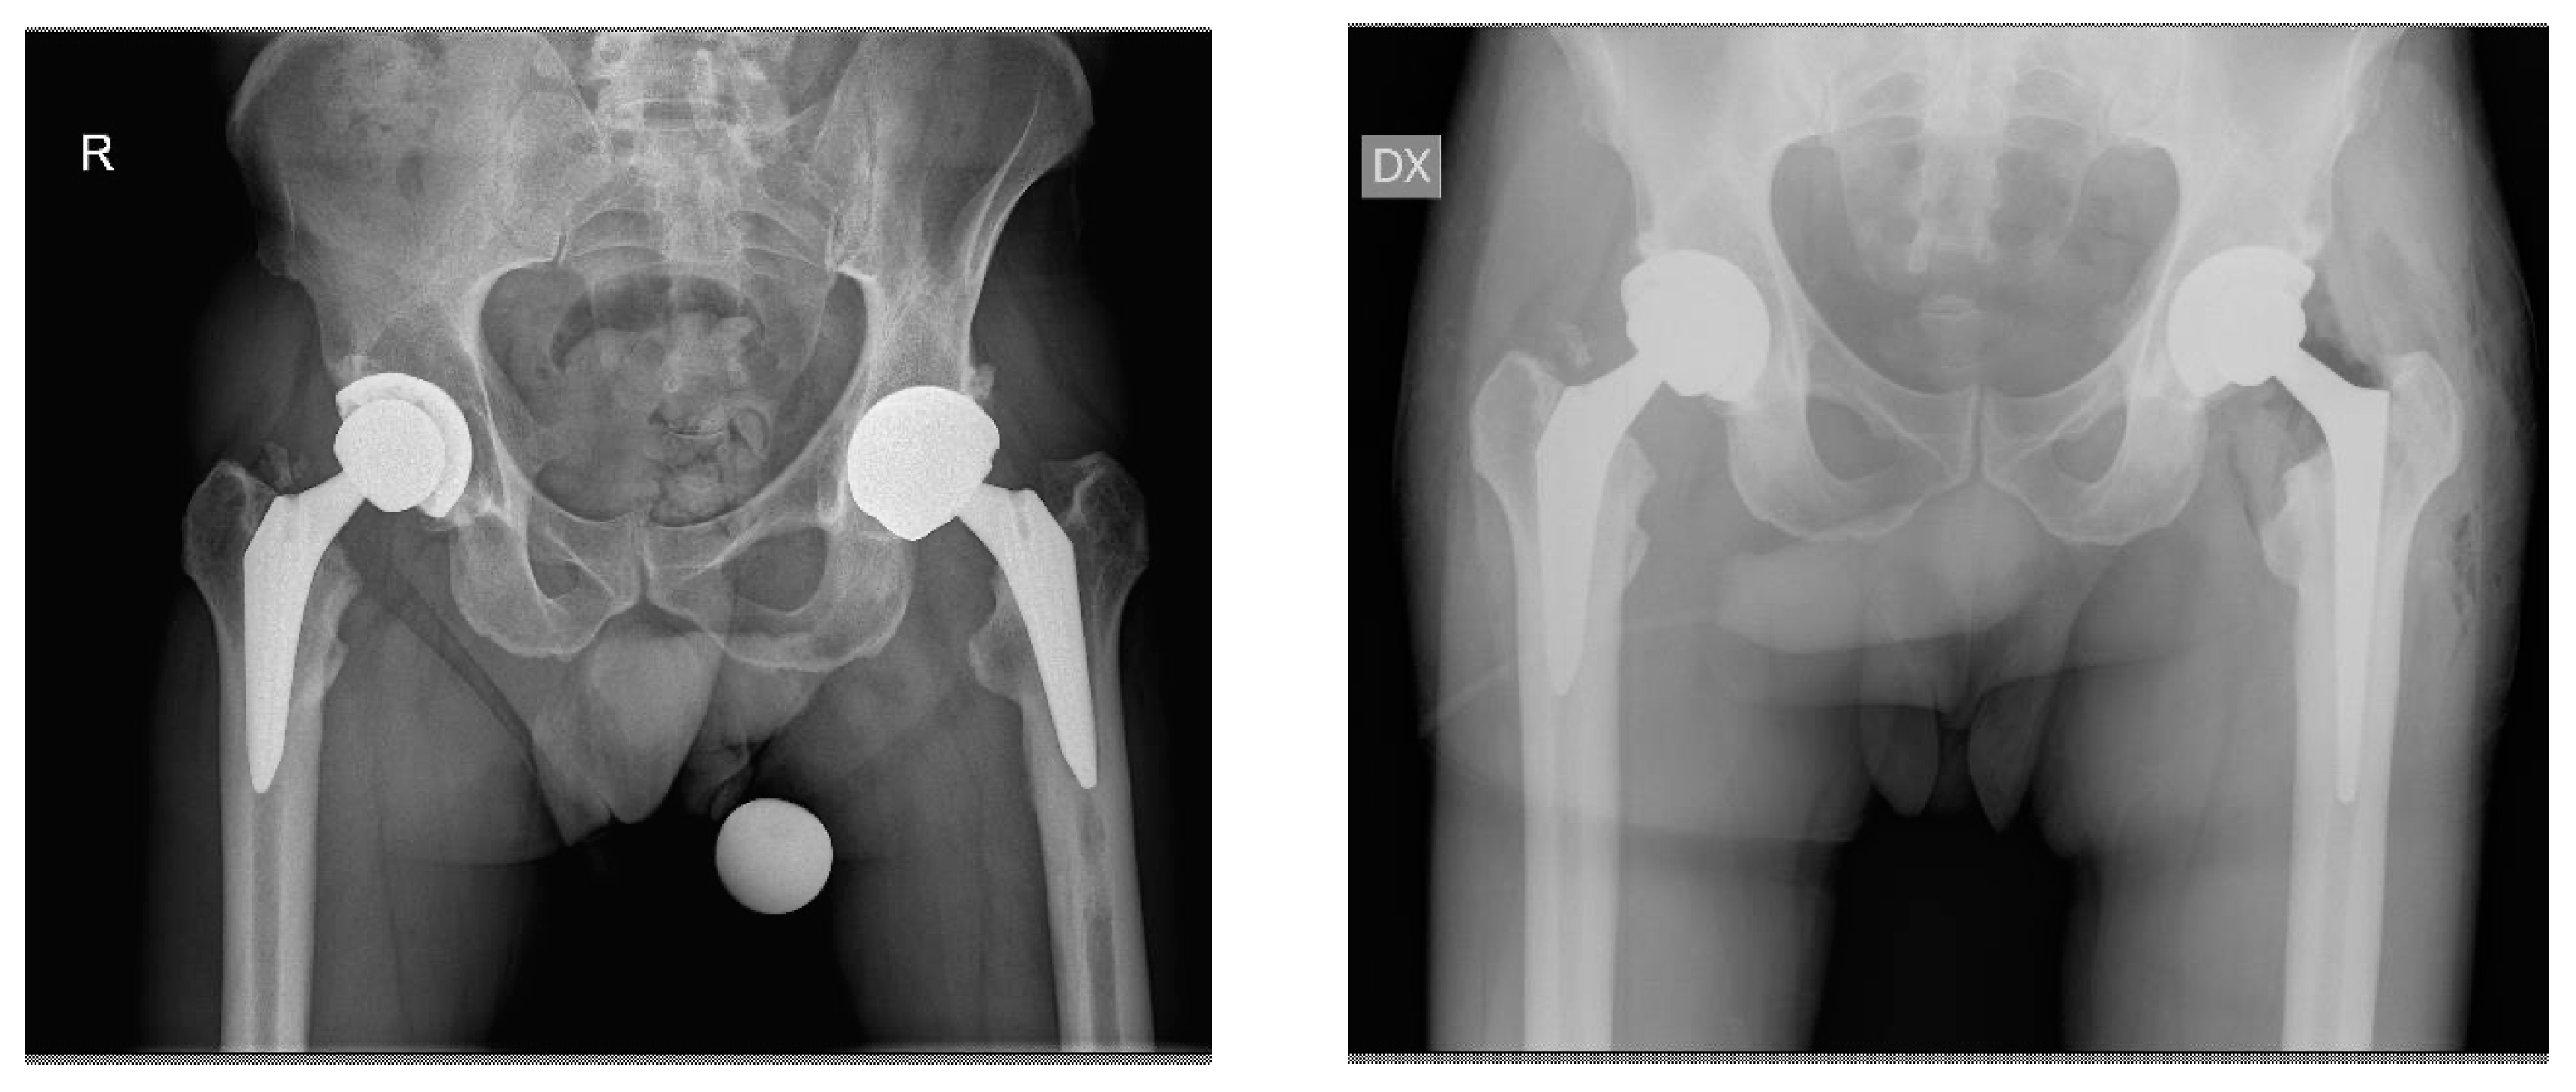

Revision of Failed Short Stems in Total Hip Arthroplasty

2.2. Surgical Technique